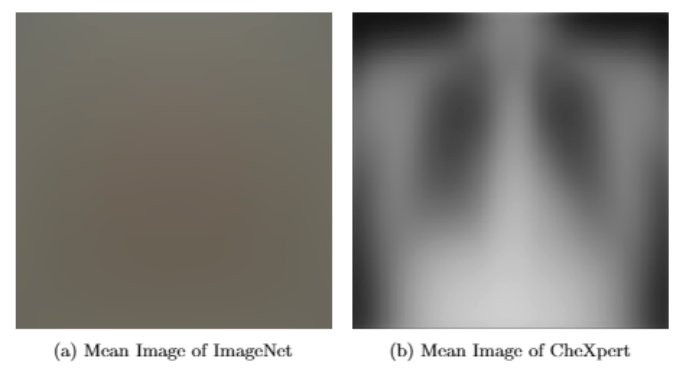

- algorithm trained at Mount Sinai Hospital, New York City

- Busy ICU, many elderly patients

- 34% of their x-rays came from patients with pneumonia

- 93% accuracy

- tested at other sites, pneumonia ~1% of x-rays

- accuracy dropped to 73%-80%

Issues with Computer Vision

At Mount Sinai, many of the infected patients were too sick to get out of bed, and so doctors used a portable chest x-ray machine. Portable x-ray images look very different from those created when a patient is standing up. Because of what it learned from Mount Sinai’s x-rays, the algorithm began to associate a portable x-ray with illness. It also anticipated a high rate of pneumonia.

The Unique Problems of Medical Computer Vision

This is the very unique problem of medical computer vision: we are attempting to solve a small signal on the background of small noise whereas standard computer vision’s problem is a large signal on the background of large noise.